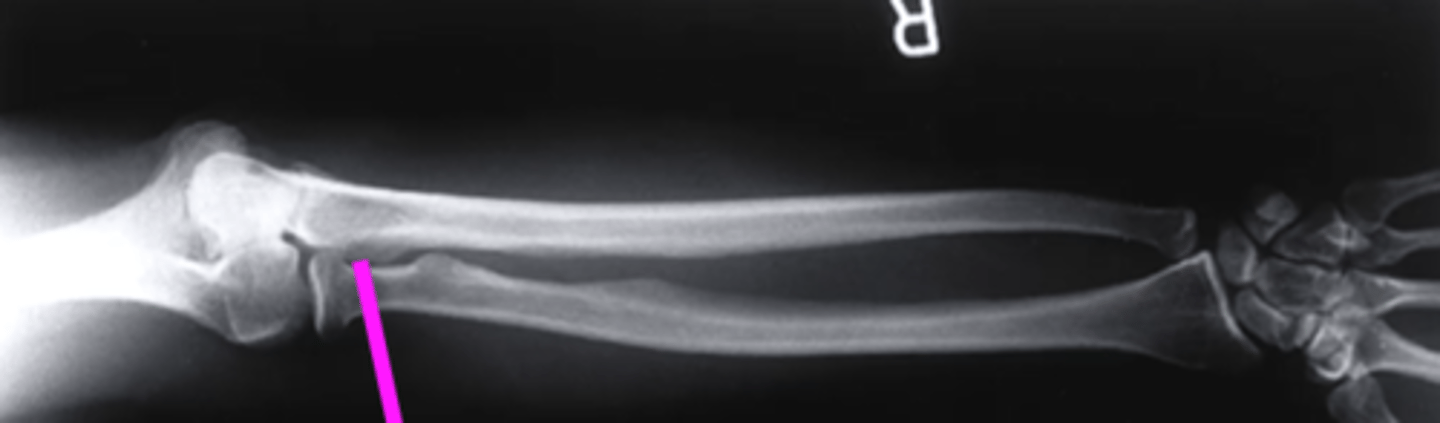

lateral forearm

what view is this

olecranon process

what does this pink line point to?

ulna

radius

radiocarpal joint